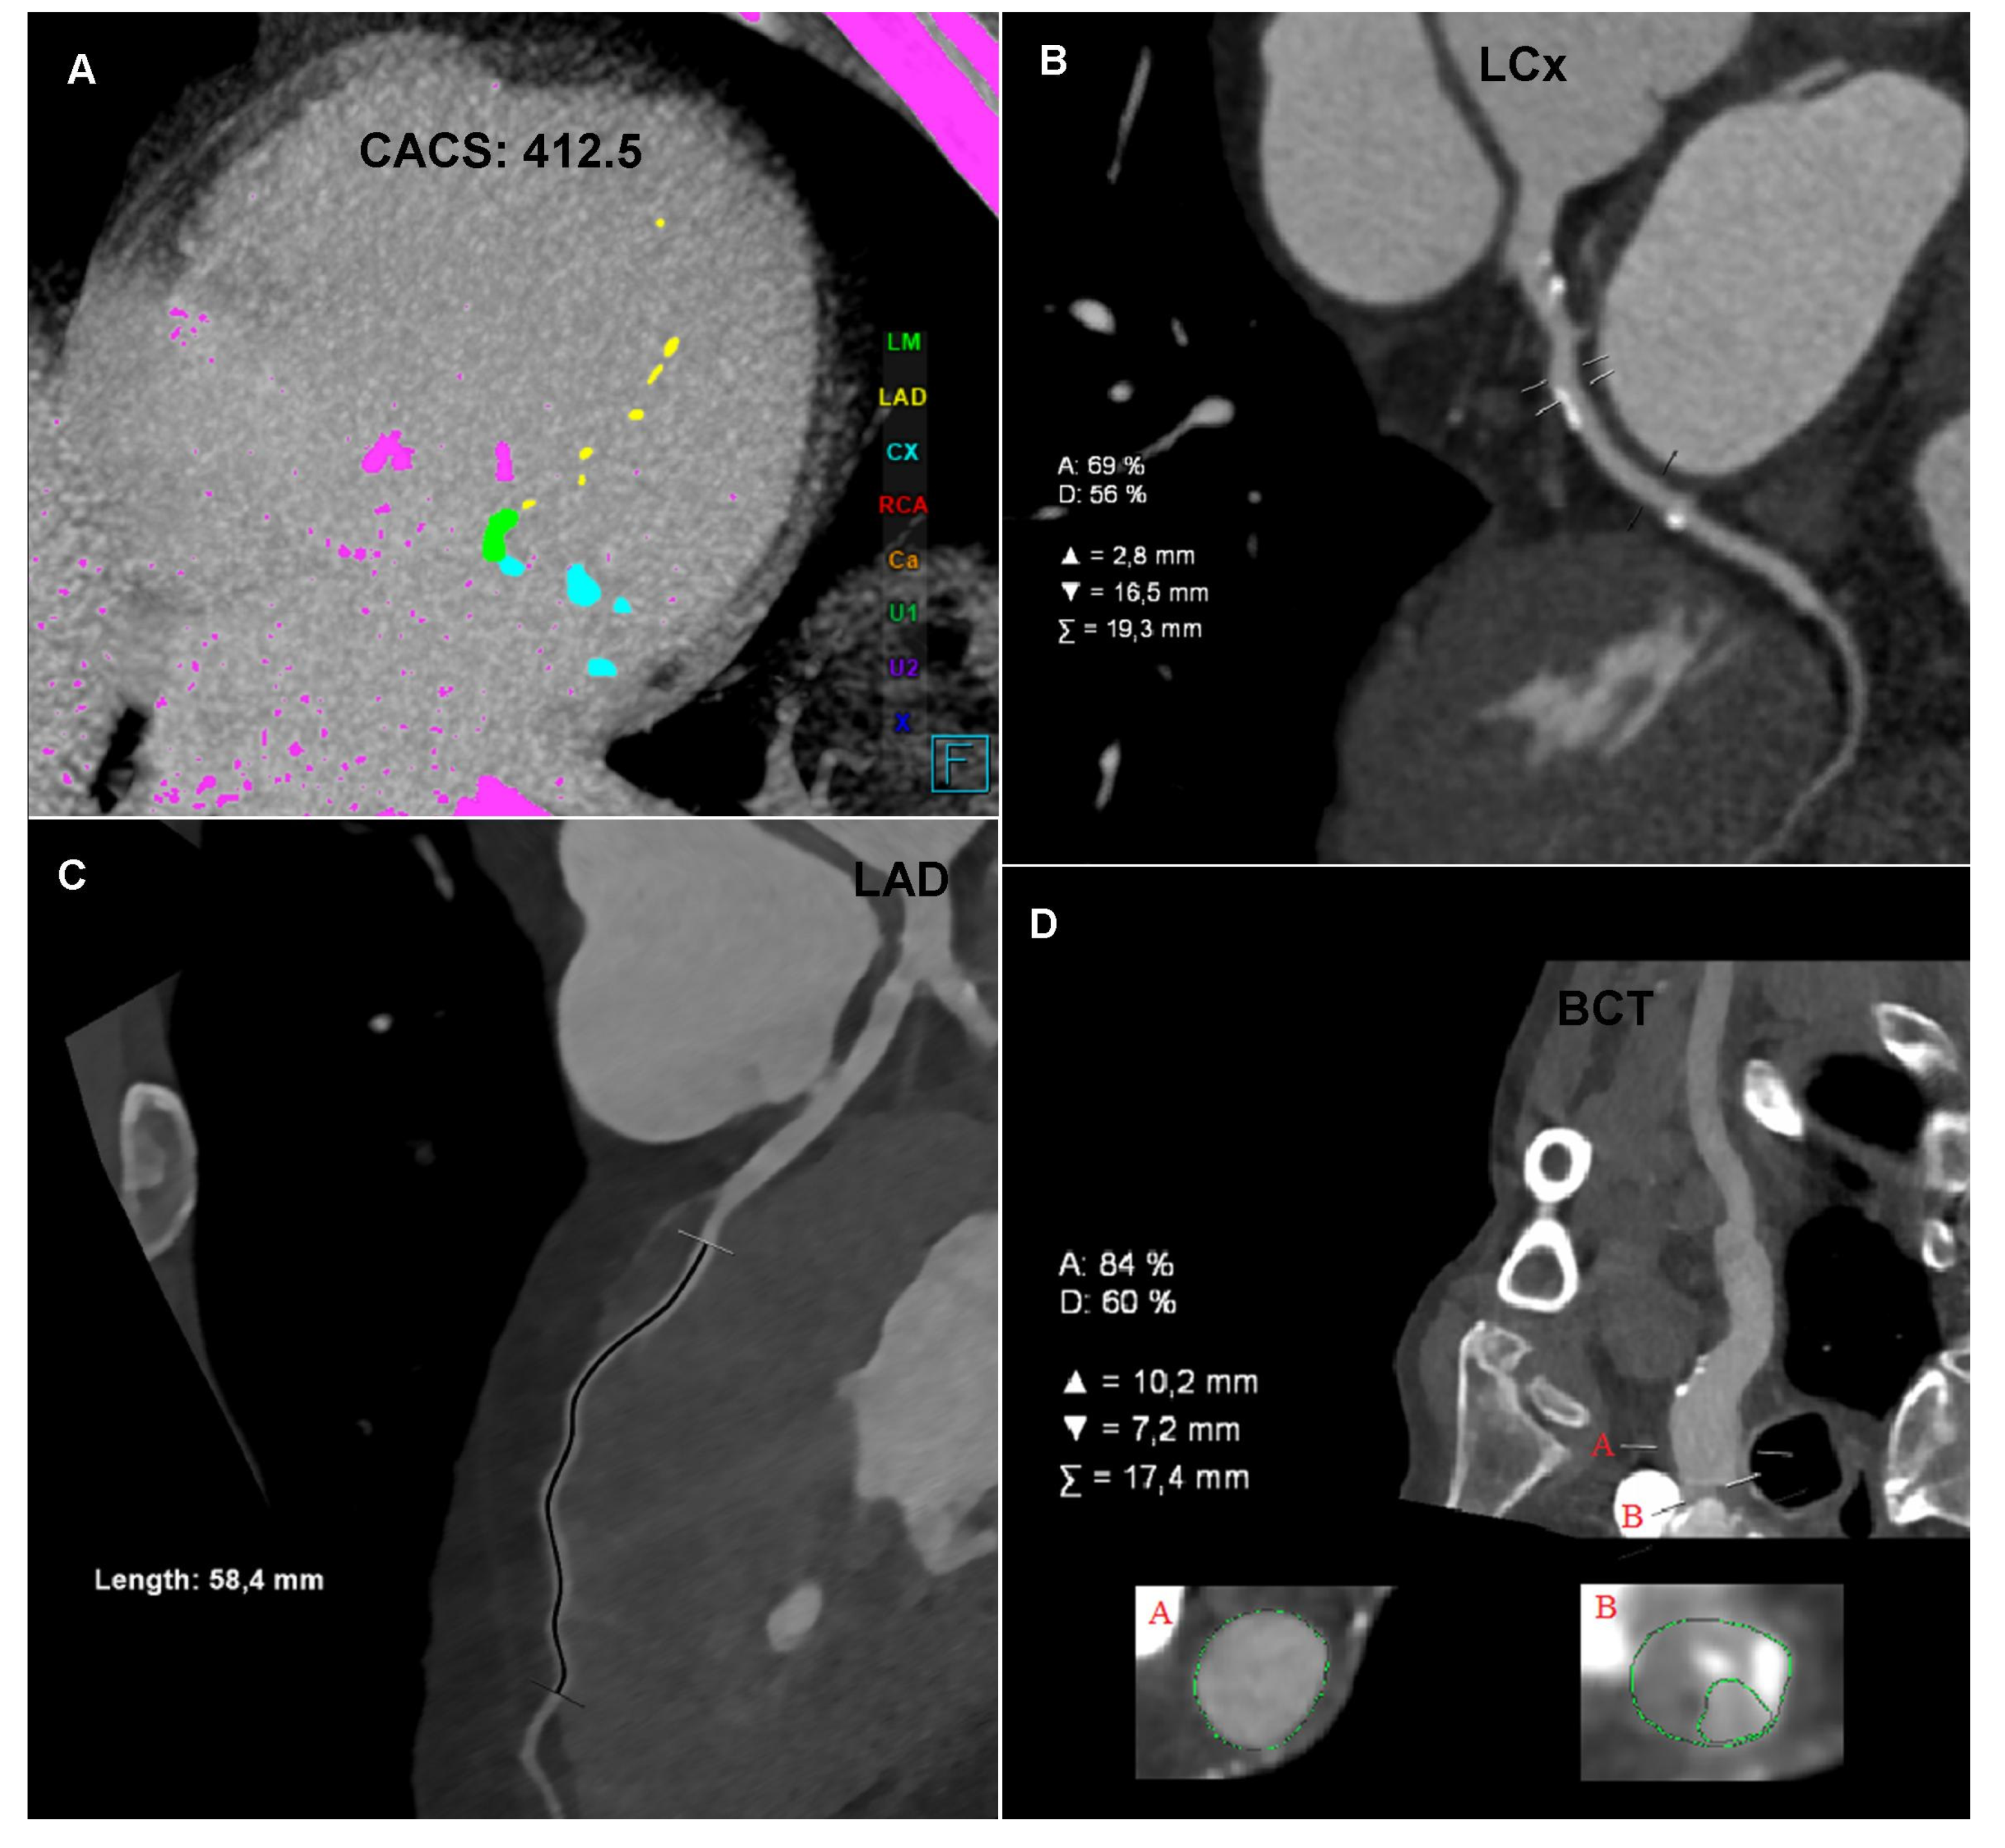

Computed tomography angiography (CTA): (A) Coronary CTA. Native phase. Axial reconstruction. Coronary artery calcium score measurement. The colors indicate the calcifications assigned to specific coronary arteries. (B) Coronary CTA. Angiographic phase. Curved multiplanar reconstruction (cMPR). Left circumflex (LCx). Measurement of the degree of stenosis. (C) Coronary CTA. Angiographic phase. Curved multiplanar reconstruction (cMPR). Left anterior descending (LAD). Measurement of the length of the myocardial muscle bridge. (D) Carotid CTA. Angiographic phase. Curved multiplanar reconstruction (cMPR). Brachiocephalic trunk (BCT). Measurement of the degree of ostial stenosis. The letter A indicates the level of vessel lumen measurement at the reference level, the letter B indicates the level of vessel lumen measurement at the level of maximum stenosis. Computed tomography angiography (CTA): (E) Carotid CTA. Angiographic phase. Volume rendering technique reconstruction (VRT). Arrows mark the recessive right vertebral artery (RVA) and the dominant left vertebral artery (LVA). (F) Carotid CTA. Angiographic phase. Curved multiplanar reconstruction (cMPR). Left subclavian artery (LSA). Measurement of the degree of stenosis. (G) Carotid CTA. Angiographic phase. Axial reconstruction. Measurement of the density of the proximal sections of the internal carotid arteries. Lower density of contrasted blood in the right carotid arteries. (H) Carotid CTA. Angiographic phase. Axial reconstruction. Measurement of the density of the cerebral arteries. Lower density of contrasted blood in the right cerebral arteries.

The CTA of the carotid and vertebral arteries performed using a 384-slice Siemens Force CT revealed a typical origin system of the aortic arch branch, numerous atherosclerotic plaques of various morphotic types in the aortic arch and its branches, significant ostial stenosis of the brachiocephalic trunk by 70–90% of the vessel lumen (Figure 1D), recessive right vertebral artery (Figure 1E), and ostial insignificant stenosis of the left subclavian artery (Figure 1F). In the CTA the right carotid arteries and the right cerebral arteries were characterized by a significantly lower lumen density compared to the contralateral side (Figure 1G,H), which may indicate impaired flow or its direction reversal. The CTA image of the carotid and vertebral arteries corresponded to significant stenosis of the brachiocephalic trunk with symptoms of the steal syndrome.